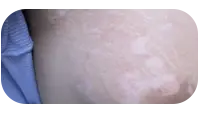

接触花粉后宝宝长了白斑

宝宝接触花粉后出现白斑,可能是花粉过敏引发的炎症后色素减退,也可能是白癜风的诱发表现。花粉作为常见过敏原,接触后可能引起皮肤炎症反应,损伤黑色素细胞导致色素脱失。婴幼儿皮肤娇嫩,免疫系统发育不完善,更容易受到影响。家长需观察白斑特点,炎症后色素减退通常边界模糊、有细小鳞屑,能自行恢复;白癜风则边界清楚、表面光滑。发现宝宝皮肤变白,应及时到正规医院检查,明确诊断后对症处理,避免延误治疗时机。